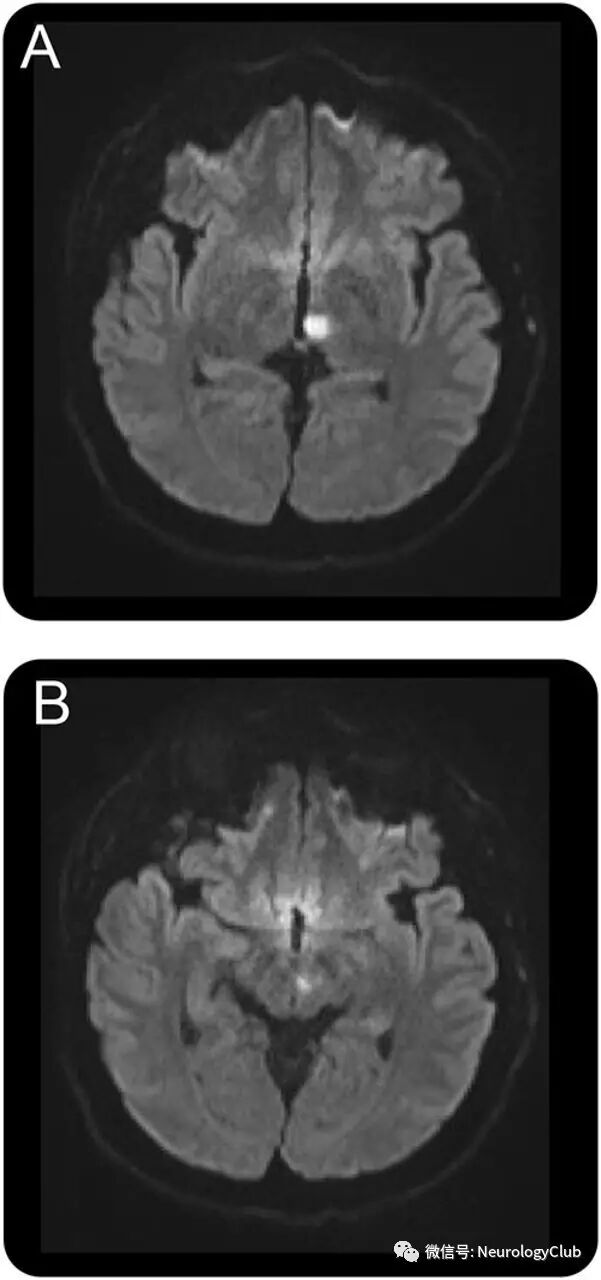

32岁男性,表现为意识模糊和复视。查体提示完全性垂直凝视麻痹伴相对保留的垂直前庭眼球反射,上视时会聚性眼震,交替性内收肥厚性反向偏斜,右眼外展受限伴内斜视,以及右侧肢体共济失调(视频)。MRI提示左侧丘脑旁中央梗死(图1)。垂直性凝视麻痹是因内侧纵束喙侧间质核损害所致。对侧内收受限符合假性外展神经麻痹,归因于下行中脑抑制会聚通路破坏。卒中机制被认为是一种罕见心血管畸形来源的反常栓子(图2)。

(图2:异常血管[白箭]连接门静脉和肺静脉,导致门-体双向分流;因缺乏血管危险因素,也不存在高凝状态,卒中机制最可能为部分型肺静脉异位连接血管短暂性血栓栓塞)